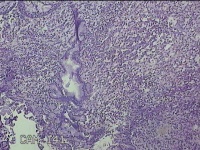

右侧鼻腔新生物

性别

女

年龄

37岁

临床诊断

1.慢性鼻窦炎 2.鼻腔新生物 3.变应性鼻炎

一般病史

鼻塞、脓涕1月。

标本名称

大体所见

灰白暗红色肿物1.3x0.7x0.3cm一个,表面光滑,切面灰白粉红色,质软。